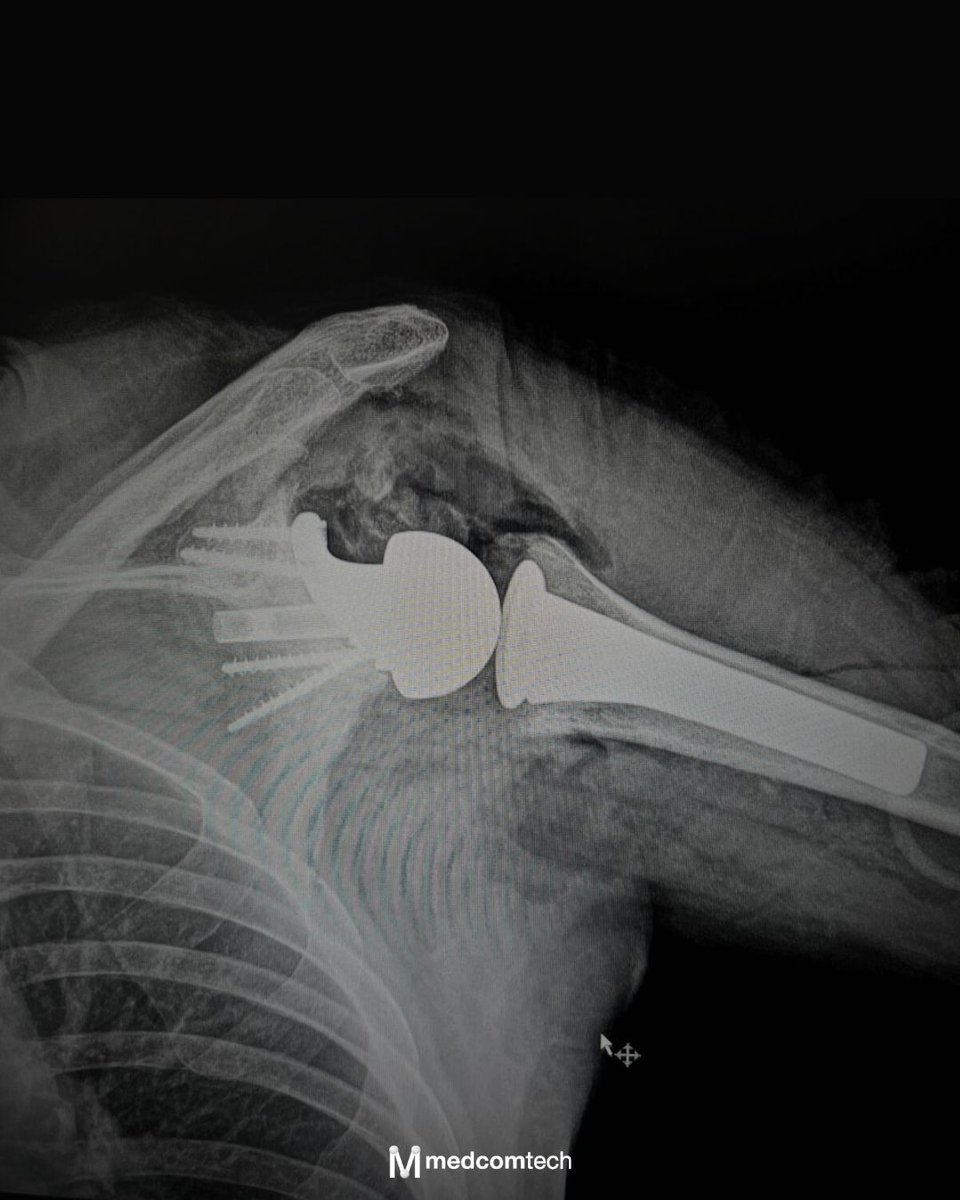

Nuevo caso de reconstrucción compleja de hombro con solución personalizada de @valor_implant

En @imed_hospitales se ha realizado una cirugía de prótesis invertida de hombro en un caso de gran defecto glenoideo que requería una solución específica de reconstrucción.